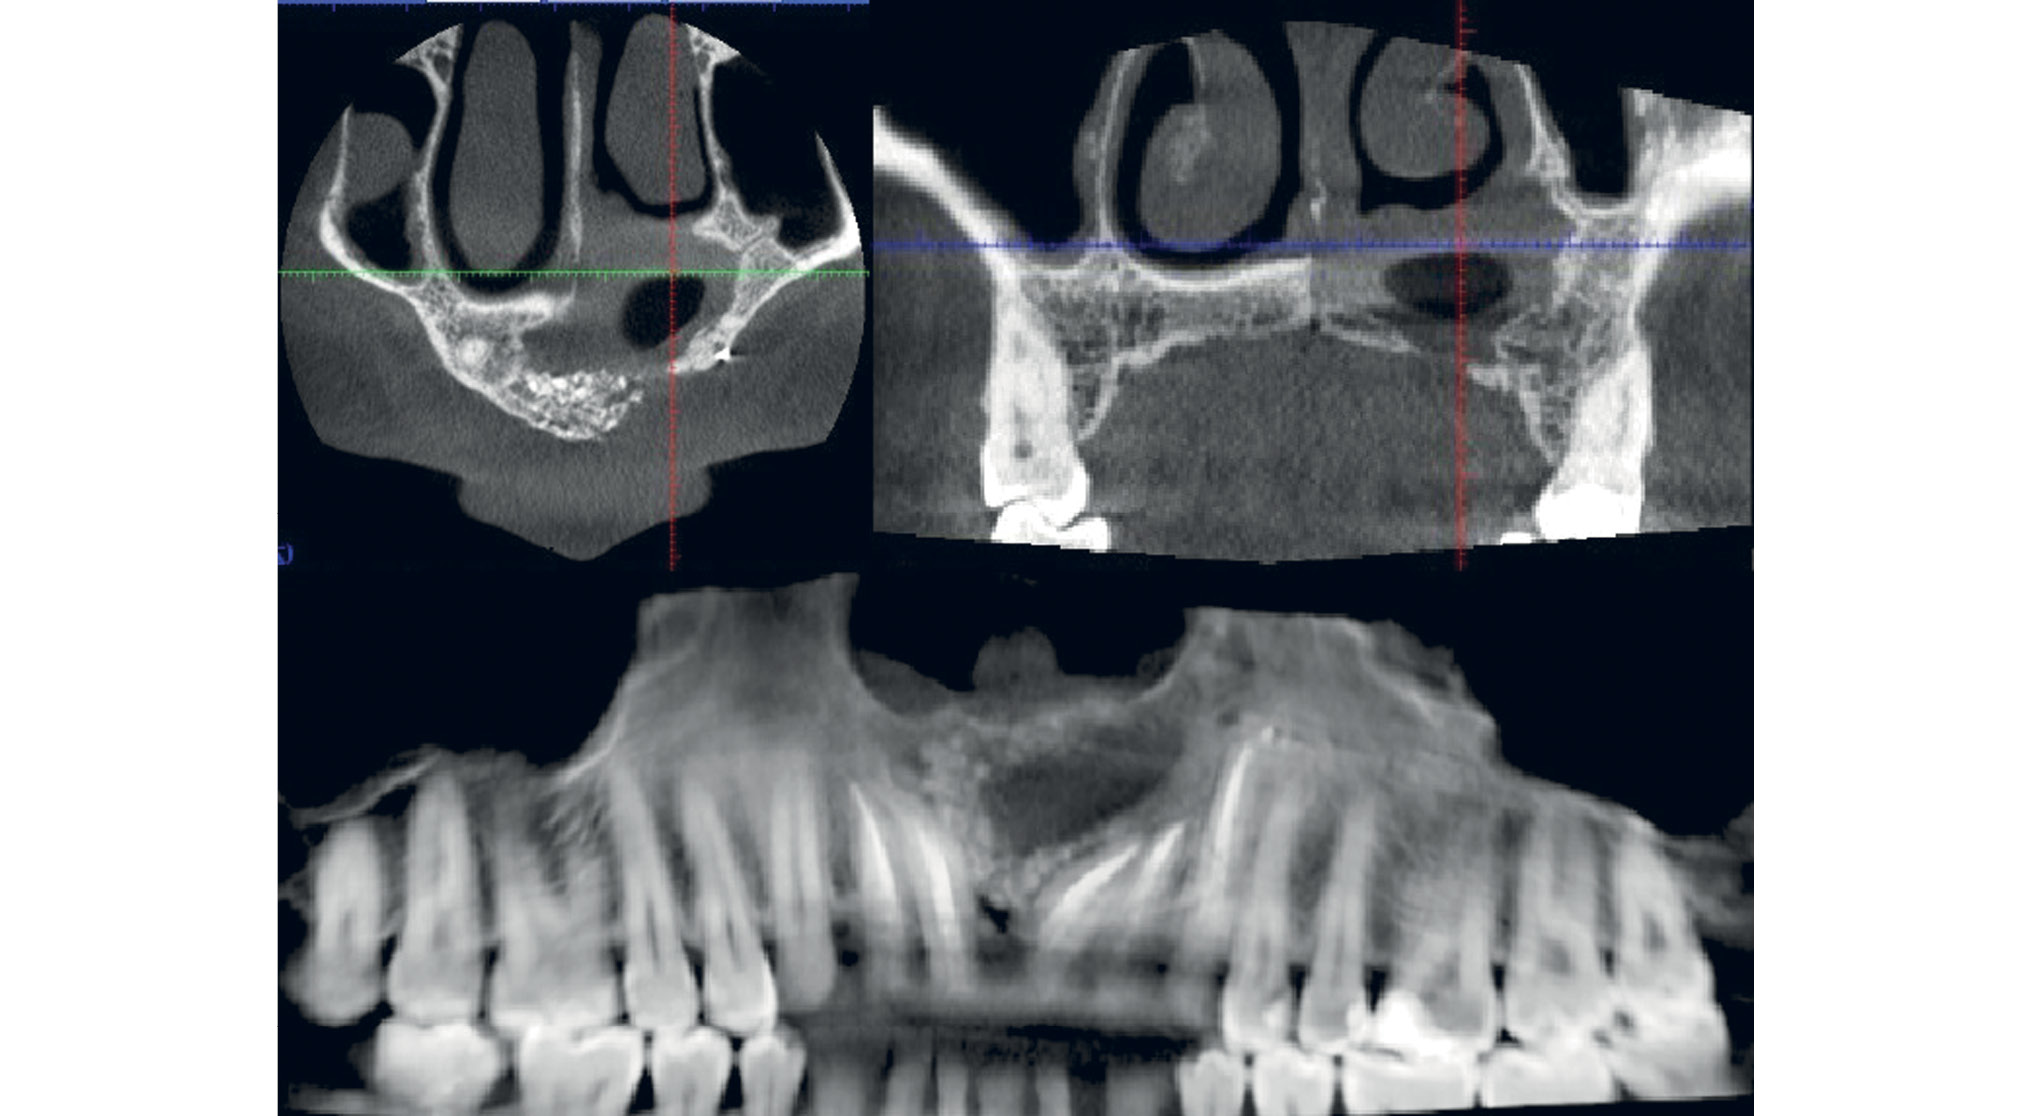

В период подготовки пациента к плановой операции было проведено предварительное эндодонтическое лечение зубов (1.2-2.3), которые прилежат корнями в полость кисты, корни зубов не лизированы. Данные о качестве эндодонтического лечения представлены на рис. 2.

Рис. 2. Пациент Д., 33 года: данные конусно-лучевой компьютерной томографии. Результат удовлетворительно проведенного эндодонтического лечения зубов 1.2-2.3, прилегающих к полости кисты, спустя 1 мес

Для исключения возникновения возможных инфекционно-воспалительных осложнений после эндодонтического лечения выжидали 1 мес. После контрольного исследования, подтвердившего качество эндодонтического лечения (см. рис. 2), было принято решение о выполнении оперативного вмешательства — удалении фолликулярной кисты с пластикой дефекта кортикальной пластинки отростка верхней челюсти титановой сеткой.